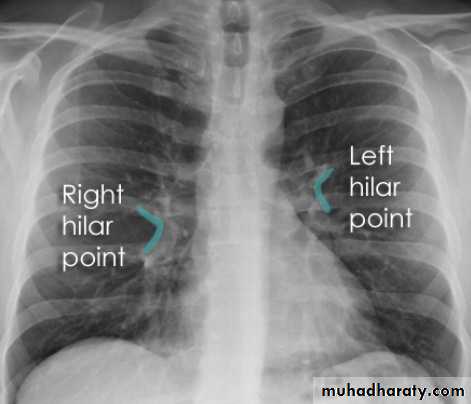

Hilar structuresThe hila (lung roots) are complicated structures mainly consisting of the major bronchi and the pulmonary veins and arteries. These structures pass through the narrow hila on each side and then branch as they widen out into the lungs. The hila are not symmetrical but contain the same basic structures on each side.

The left hilum is often higher than the right

Both hila should be of similar size and density. If either hilum is bigger and more dense, this is a good indication that there is an abnormality.